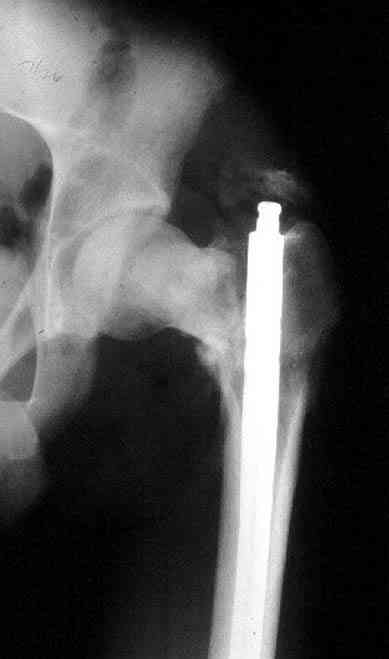

Имя     : missed neck.JPG

Имя     : ipsilateral neck shaft.JPG

Имя     : ipsilateral neck shaft nonunion.JPG